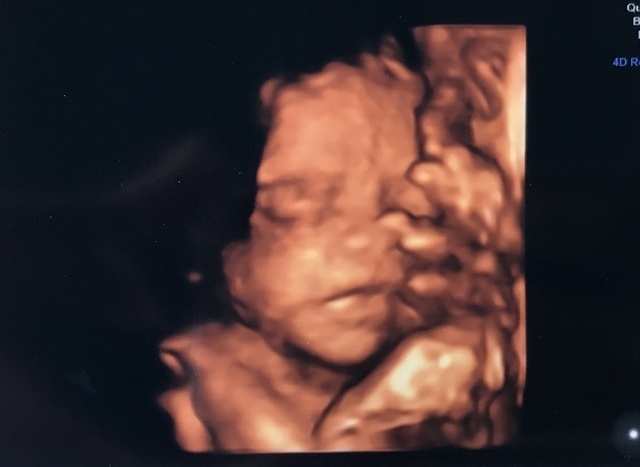

25週0日(25w0d・男の子)|まぁりん さん(31歳)

エコー写真撮影時のエピソード:

初めて顔の様子がハッキリわかった4Dエコーです!それまでなかなか4Dエコーをしてもらえず、ずっと顔が見たいと思っていました。里帰り先の産婦人科で撮っていただいたものです。旦那もこのエコー写真を見てとても喜んでいました。

私は4回の流産を経てやっとここまできたので、エコー写真をもらうたびにうれしくてたまりません!これからも大切に育てていきます。大きくなぁれ!